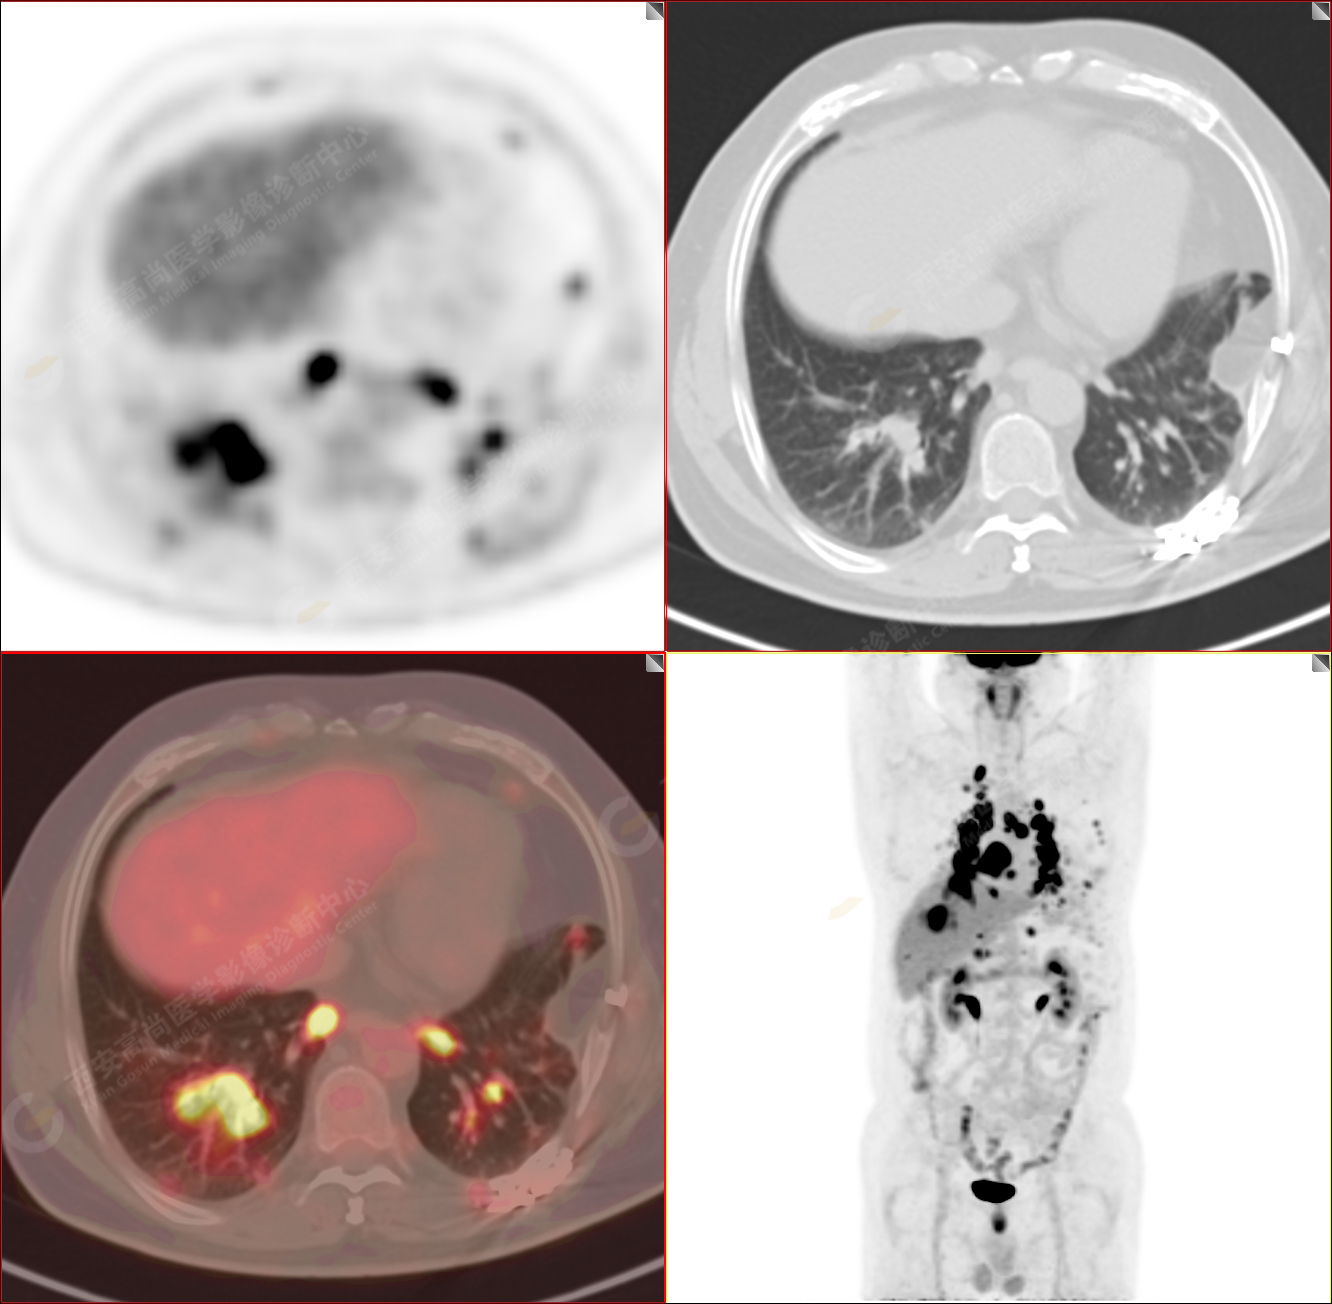

男性,53歲,頭暈半月入院,CT發(fā)現(xiàn)肺內(nèi)腫塊,雙肺多發(fā)大小不等實性及粟粒樣結(jié)節(jié),雙肺門及縱隔多發(fā)腫大淋巴結(jié)。病程中無發(fā)熱、胸悶氣及胸部不適。既往:左側(cè)肋骨外傷史。

PET/CT圖像